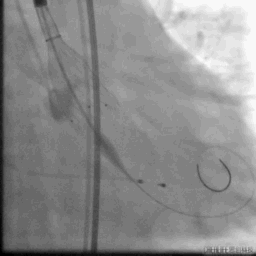

主动脉根部造影

最后一枪造影